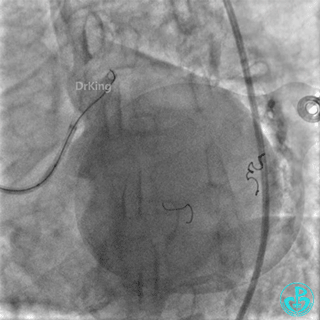

右冠脉支架通畅无狭窄,右冠脉给前降支远端提供逆向侧支循环。

EBU指引导管左冠脉造影显示粗大前降支中段闭塞,闭塞段近端有对角支发出,前降支同侧逆向显影,闭塞段不长。